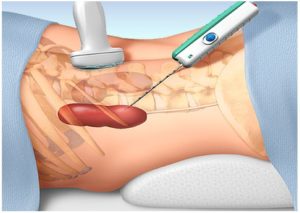

Annak érdekében, hogy megszüntesse a nagy ciszta gyakran végzett műtét az elmúlt években erre a célra elvégzett laparoszkópos sebészet - a hasfal, hogy a kis lyukak, és rajtuk keresztül a szervezetbe kerül bevezetésre laparoszkópia és egyéb szükséges eszközöket. A beavatkozás után a beteg továbbra is egy ideig felügyelete alatt a szakemberek.

A laparoszkópos sebészet - egy non-invazív módszer az innováció. amely lehetővé teszi, hogy teljesen eltávolítani a ciszta parenchyma. Módszerek művelet során bevezetésével egy speciális anyag bővül az operált területen. ami után bevezetett laparoszkópia. Elvégezhető laparoszkópos ellátjuk. azaz eltávolítjuk a ciszta parenchyma részével együtt a vese szövetben. A műtét után, a beteg van rendelve antibiotikumos kezelés és a fájdalomcsillapítók. Ha szükséges, a kezelés lehet előírni gyulladáscsökkentő szerek. A varratokat általában eltávolítják egy héttel a műtét után. A szövődmények megelőzése. Ez azt mutatja, a beteg légzési gyakorlatokat.